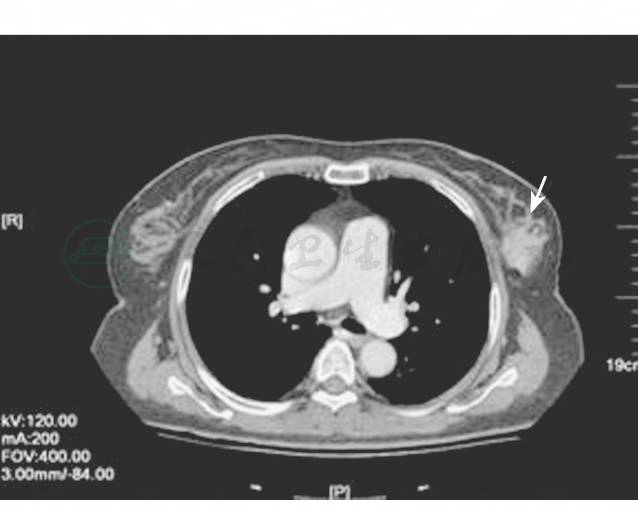

(2)第三个周期TC方案化疗后,乳腺CT提示左乳肿物和左腋窝、锁骨上淋巴结都有缩小(图5~图9)。

图9 局部晚期乳腺癌新辅助化疗后CT改变5